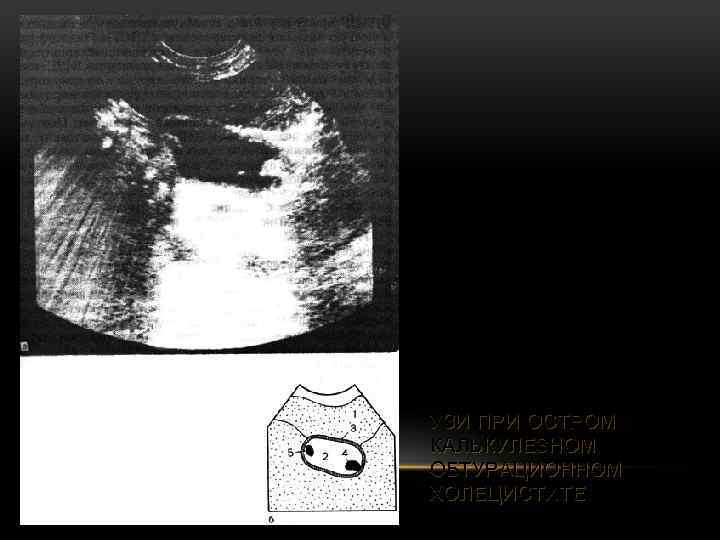

УЗИ ПРИ ОСТРОМ КАЛЬКУЛЕЗНОМ ОБТУРАЦИОННОМ ХОЛЕЦИСТИТЕ

УЗИ ПРИ ОСТРОМ КАЛЬКУЛЕЗНОМ ОБТУРАЦИОННОМ ХОЛЕЦИСТИТЕ